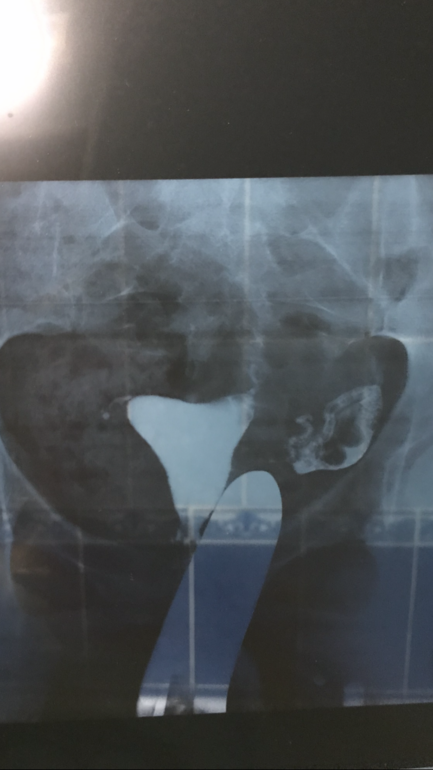

Сделали мне гсг🙏🏼

Сказали что прошла но встала в конце трубы( не вышла в полость)

Третья попытка ( ввели раствора больше чем положено) жидкость вышла но как мн объяснили она залегла в спайках😞мол это нужно лечить( введение лекарства в матку)массаж...лазеры какие то🤦🏼♀️🤦🏼♀️🤦🏼♀️🤦🏼♀️

Но трубы мне хорошо расширило прям

Это труба с констрастом в брюшной полости